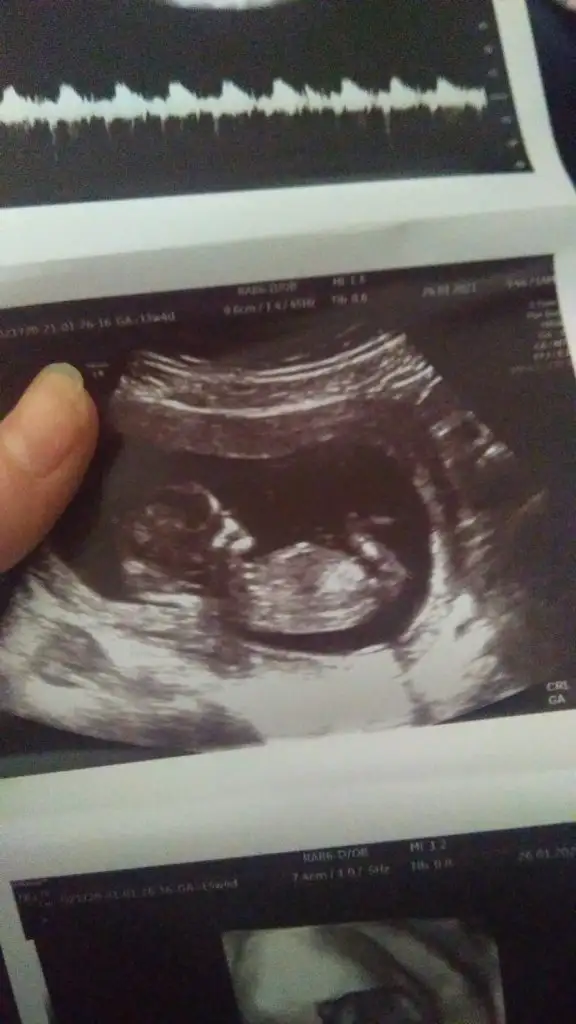

banada bakar misin canim doktorlar bir tahminde bulundular ama tam olarak demediler

7+4 teki ilk ultrason fotoğrafı tahmininiz nedir karından ultrason